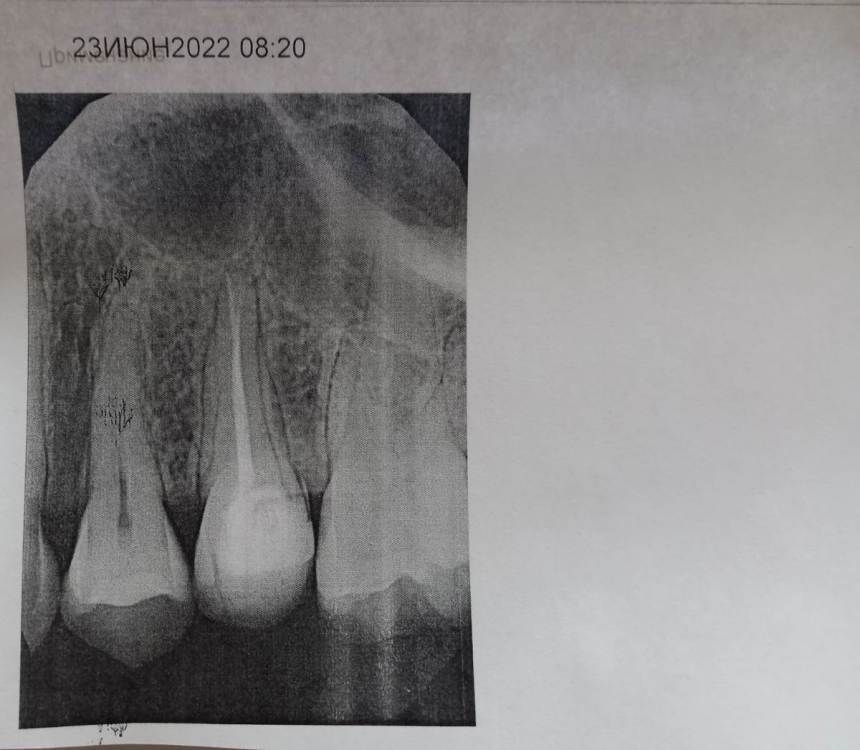

Mariaduya Опубликовано 5 июля, 2023 Поделиться Опубликовано 5 июля, 2023 (изменено) Здравствуйте. У меня сложная ситуация, боли в челюсти практически 1.5 года. Врачи не видят проблем, уже не знаю куда обратиться. Хронология. 1. В ноябре 2021 начал слегка болеть 1.6 зуб. В стоматологии мне его сразу начали депульпировать, без снимка. В ходе лечения не болел, как запломбировали каналы, постепенно появилась ноющая, постоянная боль. Я обратилась снова, сказали, что на зубе есть хроническое воспаление и ввели антибиотик туда при помощи электрофареза. Среагировал 2.5 зуб с другой стороны, и тоже начал постоянно болеть, он был депульпирован давно, но в нем развился большой кариес. 2. Мне начали их перелечивать. 1.6. не получилось пройти канал, залили резодентом, 2.5 просто переличили. 3. Боль все ещё осталась, уже в двух зубах. Врачи ничего не знают, отправили к неврологу, ЛОРУ и т.д. 4. Обошла неврологов, лоров, делала мрт, кт с контрастом головы, пазух носа, все ок. Невролог выписывает финлепсин, не помог. 5. Делала в частной клинике кт зубов, без описания, ещё не знала, что оно нужно, врач посмотрела и сказала, что видит небольшое, хроническое воспаление на 1.6 зубе и все, а так она не знает. 6. И так 1.5 года никто не знает, что со мной. Боль 1.6 и 2.5 зубы, начинают и нижние зубы болеть, уже и ухо болит. После орви болит все очень сильно, что хочется уже не просыпаться. Удалять их говорят не показаний, вдруг боль останется. Снимки в хронологии выкладываю. Есть ли на них воспаление 1.6 зуба, 2.5 зубов, есть ли них кисты свищи и все что угодно, что аномально и может вызывать боль. Может что-то с надкостницой, или суставами. Все что у меня есть - интернет, так как живу я очень далеко от нормального города и доступна только городская поликлиника, где врачи говорят, что это неврология, а невролог говорит наоборот. Сами зубы болят странно, по очереди. Если болит неделю 1.6 зуб, то 2.5 не болит и так наоборот. Вместе они не болят. Ещё странное то, что они практически симметричны друг другу по расположению. Изменено 5 июля, 2023 пользователем Mariaduya Ссылка на комментарий

Carioznik Опубликовано 5 июля, 2023 Поделиться Опубликовано 5 июля, 2023 Здравствуйте, 27 зуб надо внимательнее посмотреть, возможно там пульпит (но это неточно "бумажные " снимки малоинформативны). Скиньте лучше КТ или хотя бы ОПТГ но в электронном формате(а не фото распечатки на бумаге) Ссылка на комментарий

Carioznik Опубликовано 13 июля, 2023 Поделиться Опубликовано 13 июля, 2023 по этому старому КТ: на 16 - есть пропущенный канал, от этого, на одном из корней - есть небольшой воспалительный процесс (на тот момент). "Само не заживет", будет только расти, может, на сегодняшний момент - уже стал большой). Но жалобы в таких случаях обычно другие. Делайте новое КТ (по старому только гадать...) и снова, очный осмотр стоматолога, явно понадобится. 1 Ссылка на комментарий